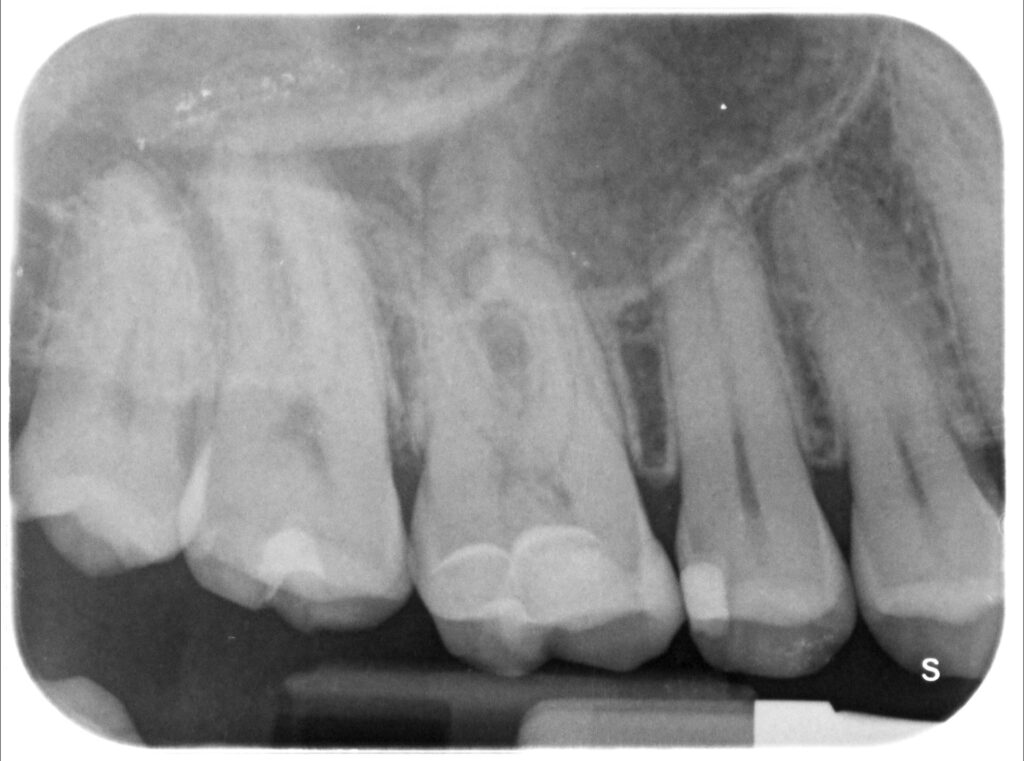

Caso clinico – trattamento ortogrado 1° molare superiore con lesione